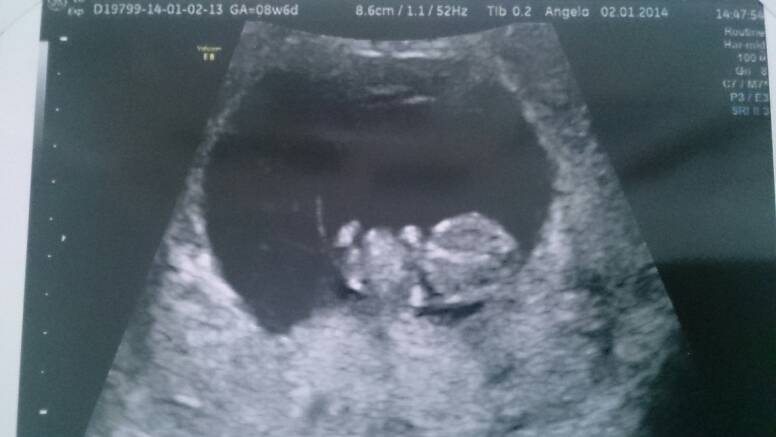

Sorki bo zdjęcie se zdjęcia..

Przez brzuch wszystkie, pierwsze 8t3 drugie dwa 8t6d.

Lilith o kurcze super widac dzidzie! Dzieki za zdjecia, to moze ja teraz tez bede sie upierac przy usg brzusznym? Sama nie wiem....W sumie to mam troche metlik w glowie, czesc osob mowi ze usg zadne nie ma wplywu na malucha, czesc mowi ze kazde usg ma wplyw a to dowcipne to juz w ogole inwazyjne grzebanie i lepiej tego nie robic.... Wkurza mnie to,mze kazdy mowi co innego, a ze jestem po stracie to jestem podatna na te wszystkie dobre rady:/:(

Lilith A zdjęcia bomba! Pierwszy raz takie widzę i nie mogę się napatrzec :D